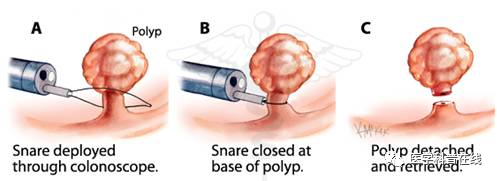

两年前,患者李女士被诊断为肠癌肝转移,先后尝试手术、化疗、生物治疗等多种治疗方式,但肝脏的病灶始终“不为所动”,并展现出一副“今日不将我消灭,明日必将汹涌而至”的态势。李女士辗转多处后至华山医院北院肿瘤科就诊,针对病灶残留,听从医生的建议决定使用“内放疗”。2个月前,梁晓华主任团队在李女士的肝病灶内成功植入了30枚碘125粒子,将病灶“团团包围”。患者术后未出现不适症状,并于隔日出院。术后2个月再次入院复查,肝内病灶明显缩小,逆转了肿瘤细胞“开疆拓土”的趋势。8Wz帝国网站管理系统

“内放疗”是一种放射性粒子植入术。医生利用现代影像学技术将具有放射性核素的粒子直接插植到肿瘤病灶内或肿瘤周围,放射性粒子通过持续释放射线对肿瘤细胞进行杀伤。“内放疗”属于高度适形放疗的一种,目前国内所应用的放射性粒子主要指碘125粒子。8Wz帝国网站管理系统

小小粒子所产生的γ射线能量虽然不大,但能持续地对肿瘤细胞进行作用,从而使肿瘤细胞全部失去繁殖能力,达到较为彻底的治疗效果。粒子治疗已经成为华山医院北院肿瘤科局部治疗的一员,针对性地治疗某些转移性肿瘤、难治性疾病,起到“歼灭顽敌” 的作用。8Wz帝国网站管理系统